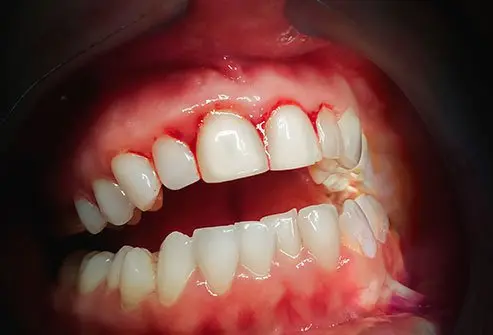

Recognizing gingivitis early can help prevent long-term complications. Common symptoms include:

- Red, swollen or tender gums

- Bleeding during brushing or flossing